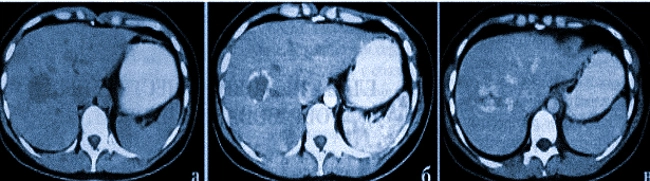

Опухоль Печени Фото

Опухоль Печени Фото 116 фото